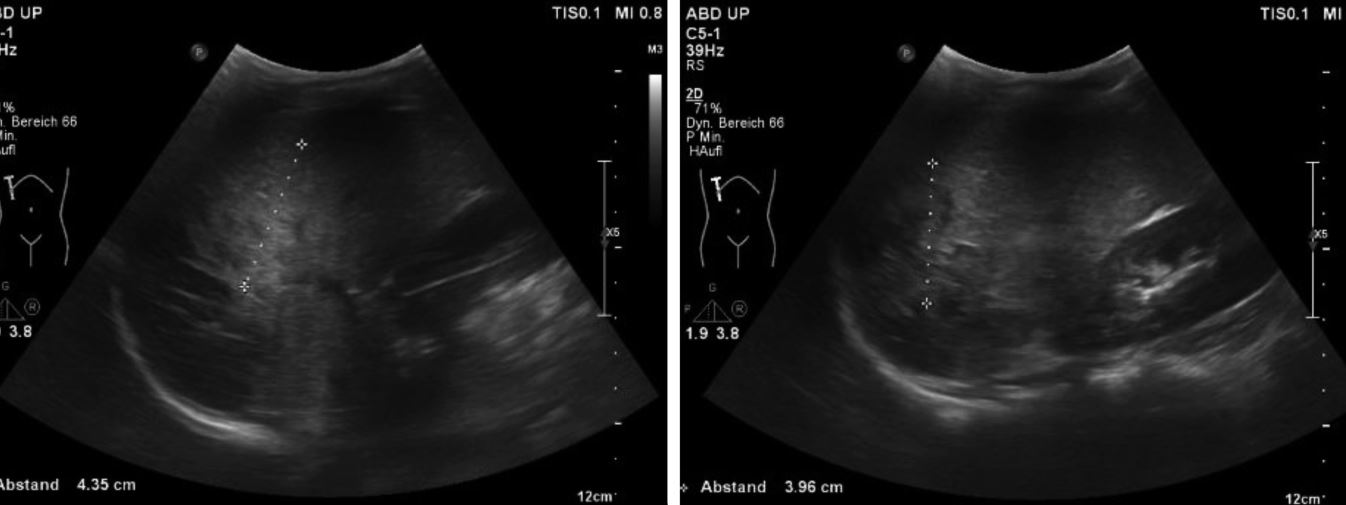

Ein neunjähriger Junge wurde nach einem Schlittenunfall notfallmäßig in der Kinderklinik vorgestellt. Sein Vater trug ihn auf dem Arm in die Notaufnahme, da der Rettungsdienst nicht verständigt worden war. Der Junge war zusammen mit einem Freund, beide ohne Helm oder Schutzkleidung, eine steile Abfahrt hinuntergefahren. Während der Junge auf dem Schlitten lag, saß sein Freund auf ihm. Die beiden prallten mit hoher Geschwindigkeit gegen einen Mast. Seitdem hatte der Junge zunehmende Bauchschmerzen. Sein Hautkolorit war blass, er atmete angestrengt und hatte einen angespannten Bauch. Seine Gelenke waren frei beweglich, aber er wirkte schmerzgeplagt und war kaltschweißig. Der Junge war allseits orientiert. Die Herzfrequenz betrug 160 Schläge pro Minute, der Blutdruck lag bei 83/65 mmHg, und die pulsoxymetrisch gemessene Sauerstoffsättigung betrug 100 %. Äußerlich waren eine Platzwunde an der Stirn (Abb. 1) und eine kleine thorakale Prellmarke sichtbar. Umgehend erfolgten eine Sonografie und danach eine Computertomografie des Abdomens (Abb. 2 und 3).

Abb. 2

: Sonografie des Abdomens

© Dr. med. Thomas Hoppen